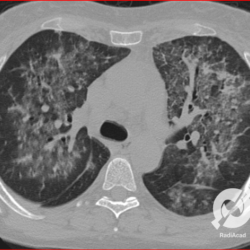

Opacidades em vidro fosco difusas com espessamento liso de septos e moderado derrame pleural bilateral.

Opacidades em vidro fosco difusas com espessamento liso de septos e pequeno derrame pleural bilateral.